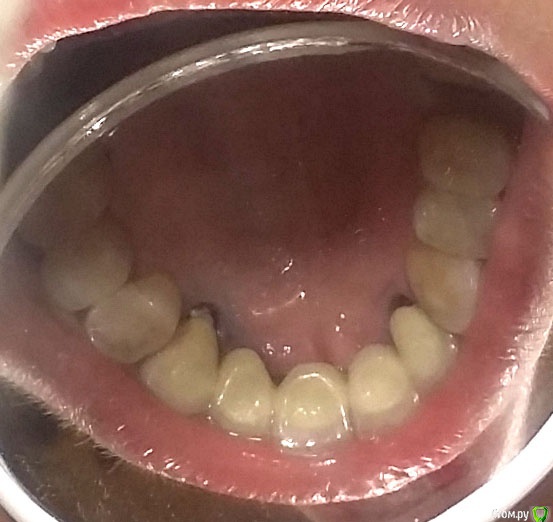

Yashika Опубликовано 25 декабря, 2015 Поделиться Опубликовано 25 декабря, 2015 (изменено) Уважаемые доктора, у меня очень короткий вопрос т.к. я не понимаю, продолжать ли мне искать доктора или я ищу чего-то невозможного На передних верхних зубах стоит мост металлокерамика (вкладки кобальт-хром) на 2 опорных. Сзади ушла десна, образовались карманы, иногда кровит. ХОЧУ ЗАМЕНИТЬ КОНСТРУКЦИЮ с учетом текущей ситуации. Сталкиваюсь с тем, что второй протезист отказывается распиливать коронки Говорят, вкладки массивные и стенки довольно тонкие, боятся в процессе сломать корни. Но я вроде бы не прошу ломом выдрать вкладки, только снять коронки. Отказываются! Говорят "ходи так пока сами не расцементируются"! А, если оно 10 лет еще не расцементируется? Подскажите, я прошу действительного невозможного? Металлокерамику разве нельзя распилить и заменить, не выдирая вкладки при этом? На снимках орто и (простите это максимум, как я могу раззявить рот и моей камеры), но думаю, примерно понятно, где ушла десна и почему хочу это все снять. Спереди все нормально, карманы только сзади. Изменено 25 декабря, 2015 пользователем Yashika Ссылка на комментарий